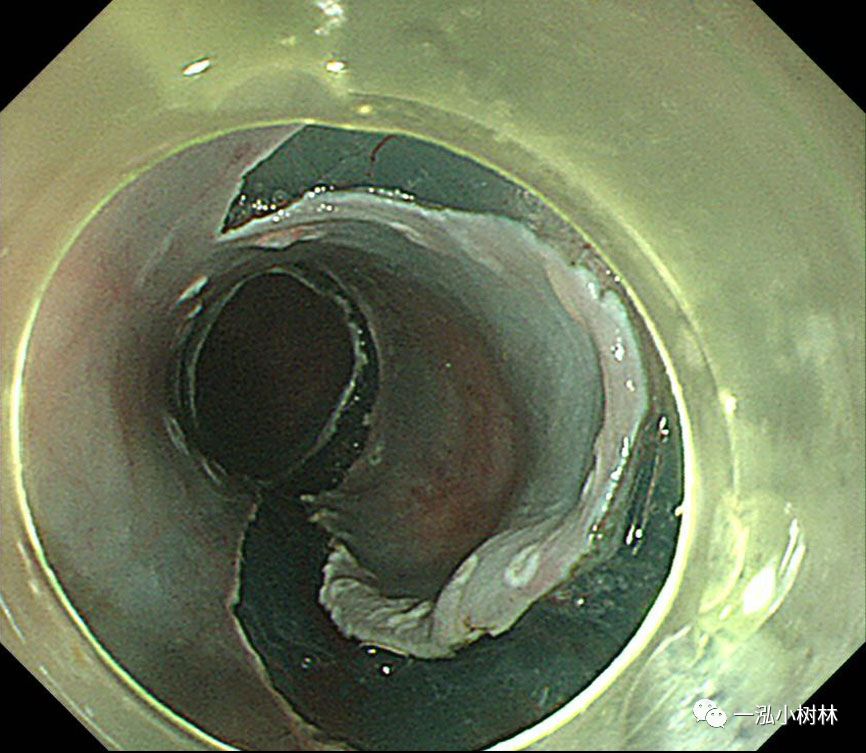

图6 在远端(肛侧)进行黏膜切口